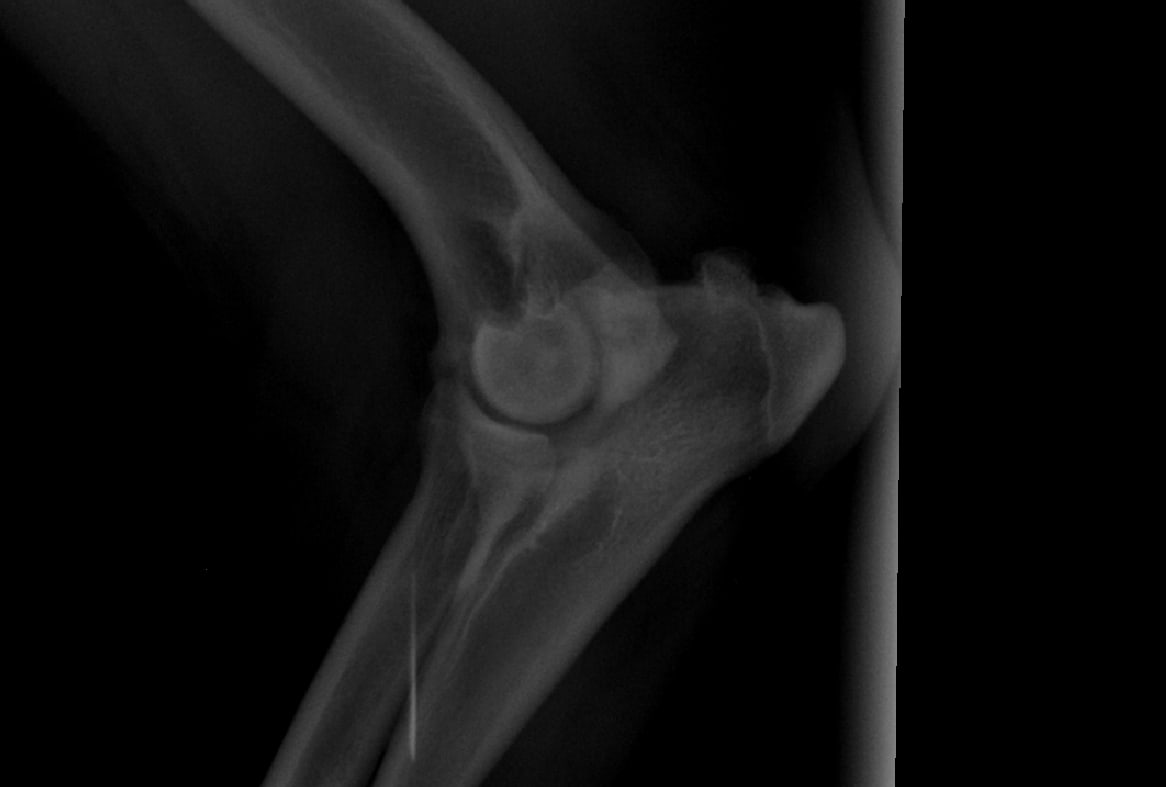

Hi, My Rottweiler is 4 years old. 10 days ago he starting experiencing excruciating pain in is right front leg. we took him to the vet where they took XRays and said he has some inflammation and looks like arthritis. They didn't do much and put him on anti inflams. its been 10 days and made no difference. I have the Xrays attached. Please help so that I know where to send him for proper help.

Hello, sorry to hear about Baloo. His elbows definitely show signs of arthritis. Elbow arthritis is common in Rottweilers has 3 components to it. 2 of these components, a fragments coranoid process and an ununited anconeal process can cause moderate to severe pain. The therapy for this disease includes surgery to remove the chipped bone fragments in the joint. You should consult with an orthopedic surgeon regarding Baloos elbow disease so that his problem can be addressed. In the mean time, you can ask your veterinarian for additional pain meds to try and help keep Baloo as comfortable as possible. Hope this helps and best of luck